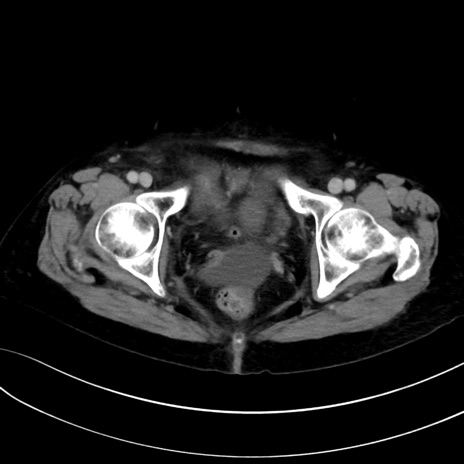

(冠状断像)1日半後